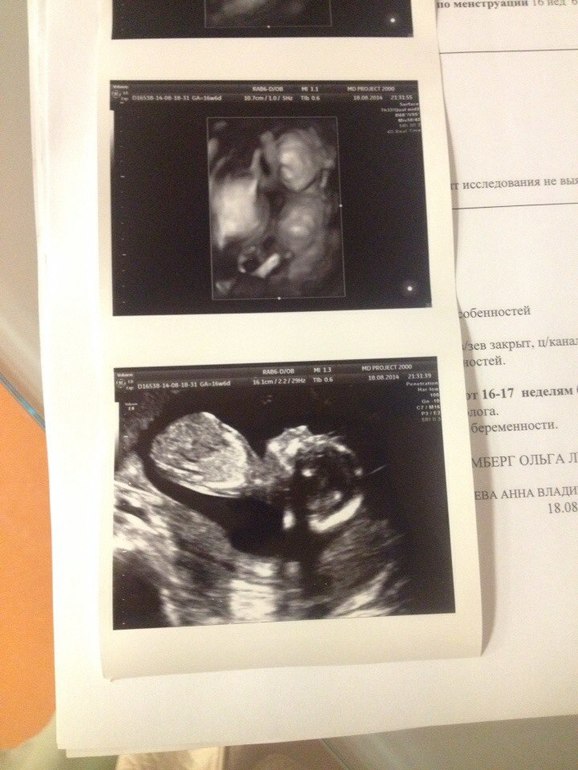

Но когда я зашла, и когда она первым же прикосновением датчика подтвердила пол, который мне сказали еще при хромосомном анализе, когда она спокойно все объясняла, где ножки, где ручки, я растаяла.

Сын так же сладко зевнул и помахал нам ручками.

В общем все у нас хорошо, слава Б-гу. Развит на свои 16-17 недель. Как раз по менструации вчера ему было 16 и 6, а по узи ранних сроков 16 и 3. Осталось в 20 недель еще убедится в том, что сердце здорово и можно слегка выдохнуть.

вообще шла просто на обычное, смысл был именно в том, чтобы попасть конкретно к Ольге Леонидовне.но она решила что малыша отлично видно, так что можно нам и 3д картинку показать.